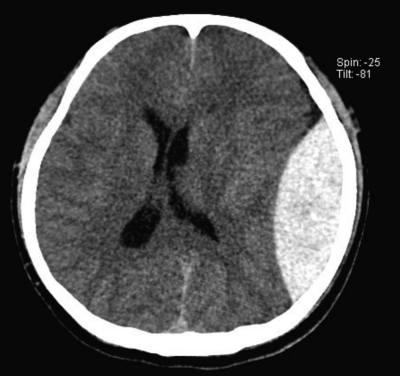

頭部CTを別に示す。出血部位について正しいのはどれか。

2. 硬膜外腔

凸レンズ型の血腫→硬膜外血腫、三日月の血腫→硬膜下血腫